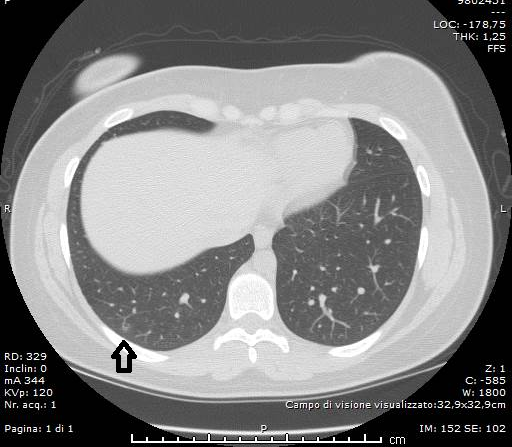

La TC ha messo bene in evidenza, inoltre, il “segno ragnatela” (“spider web sign”), rappresentato da un’area di opacità ground-glass, ad aspetto grossolanamente triangolare ed angolare, in sede basale sub-pleurica a destra, con all’interno setti interlobulari ispessiti come una rete; la pleura adiacente era stirata ed ispessita, denotando una forma simile a quella di una ragnatela nell’angolo.

Al settimo giorno di terapia il paziente mostrava un modesto, ma progressivo, miglioramento del quadro clinico e laboratoristico, con discreta diminuzione dei valori di PCR, LDH; stabile la leucopenia. In decima giornata viene ripetuta l’indagine HRCT, per rivalutare il quadro radiologico, che ha documentato, in entrambi i polmoni, una riduzione sia degli addensamenti parenchimali con aspetto “a vetro smerigliato”, che delle aree con pattern “crazy-paving”, che tuttavia erano comunque ancora presenti nei campi medi ed in sede periferica, bilateralmente. Persisteva ancora l’ispessimento/stiramento della pleura viscerale in sede basale posteriore destra, dalla quale si dipartivano setti e tralci ad aspetto fibrosclerotico. Non era più visibile il versamento pleurico.

Durante la terza settimana di cura i tamponi per la verifica dell’infezione da Covid-19 si erano negativizzati. Così, dopo aver effettuato un’altra indagine HRCT, che ha documentato la pressocchè quasi completa risoluzione TDM degli addensamenti e dei reperti patologici parenchimali polmonari bilaterali già descritti, il paziente è stato dimesso.